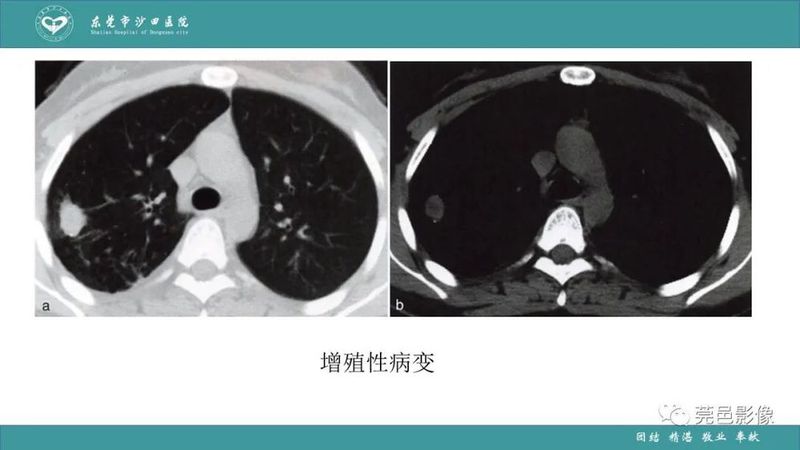

「肺炎克雷伯杆菌肺炎」影像学诊断+鉴别诊断